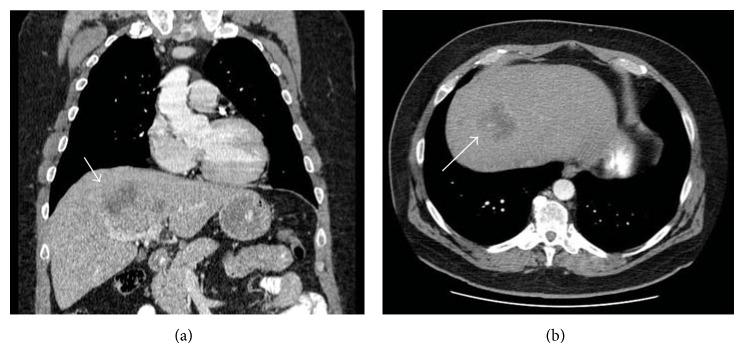

Acute liver failure (ALF) is a rare presentation of liver metastases. Although cases of ALF from metastatic disease have been reported, etiologies have been largely confined to lymphoma, metastatic breast, lung, and gastric cancers. ALF from medullary thyroid cancer (MTC) has never been reported. We present a 59-year-old male with newly diagnosed MTC, who was admitted with ALF. He presented with jaundice, hepatic encephalopathy, and synthetic dysfunction. His clinical course was marked by rapid decompensation within 6 days from initial presentation of jaundice to development of hepatic coma. Although liver metastases from medullary thyroid cancer have been reported, to our knowledge, this is the first described case of MTC resulting in acute liver failure.

急性肝衰竭(ALF)是肝转移瘤的一种罕见表现。虽然已有转移性疾病导致ALF的病例报道,但其病因主要局限于淋巴瘤、转移性乳腺癌、肺癌和胃癌。甲状腺髓样癌(MTC)导致的ALF从未有过报道。我们报告一例59岁新诊断为MTC的男性患者,因ALF入院。他表现为黄疸、肝性脑病和肝功能合成障碍。其临床病程特点是从最初出现黄疸到发展为肝昏迷在6天内迅速失代偿。虽然已有甲状腺髓样癌肝转移的报道,但据我们所知,这是首例描述的MTC导致急性肝衰竭的病例。